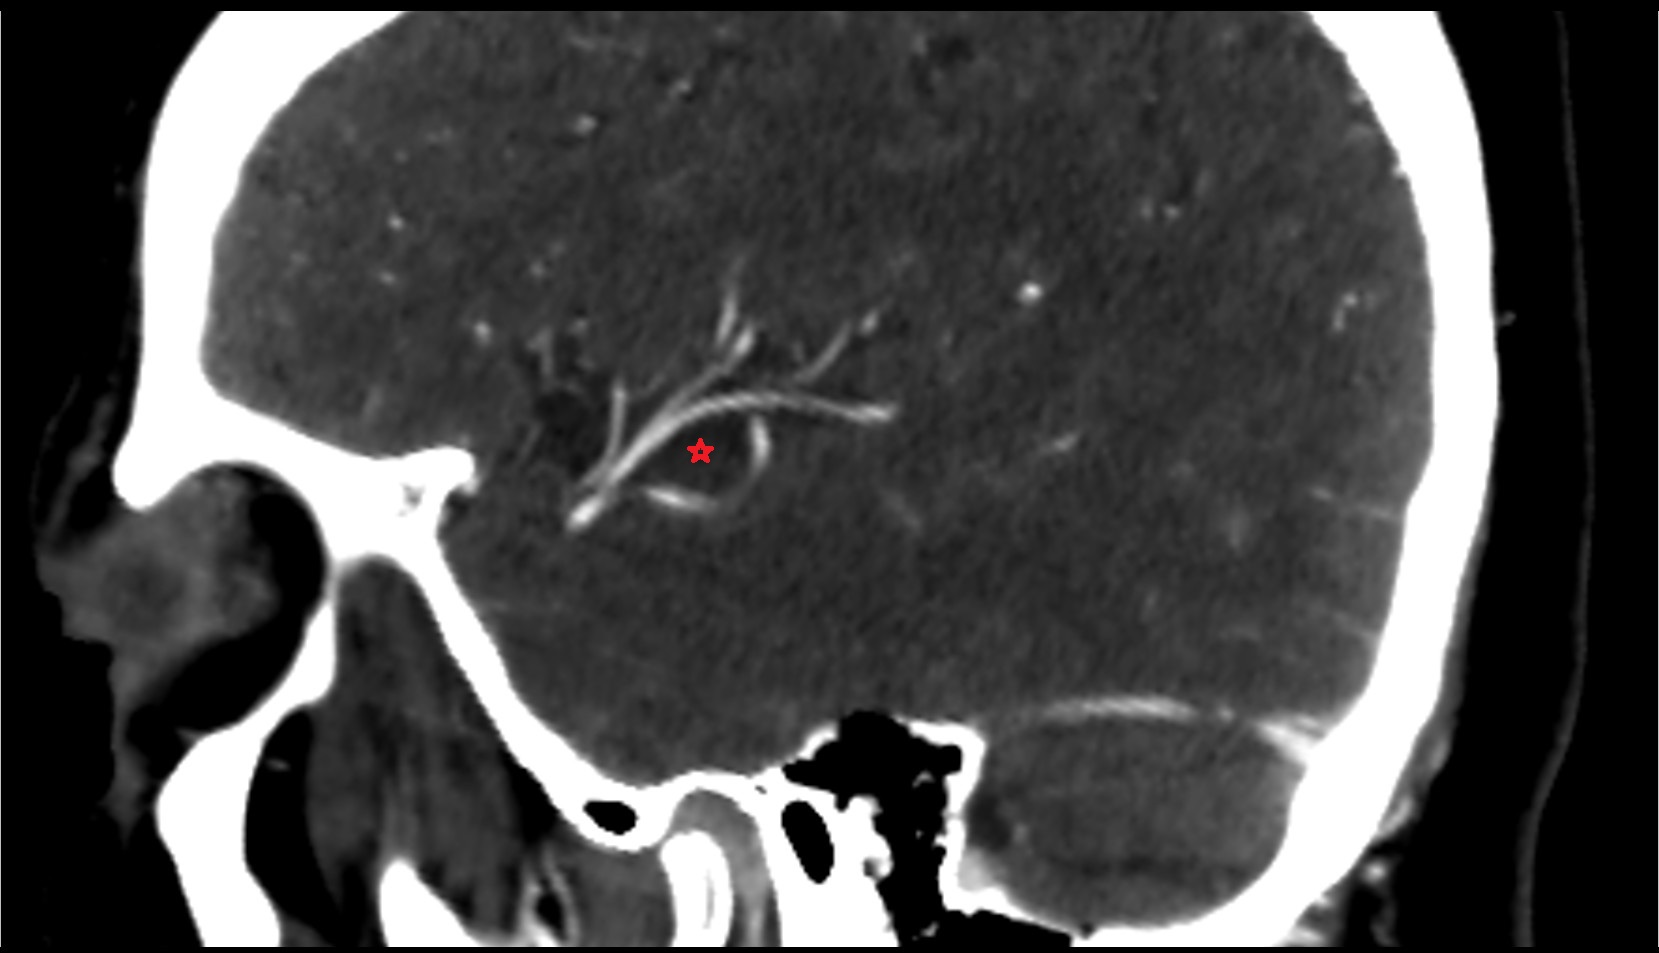

- Middle cerebral artery horizontal segment (M1)

- Middle cerebral artery insular segment (M2)

- Middle cerebral artery opercular segment (M3)

- Middle cerebral artery cortical segment (M4)